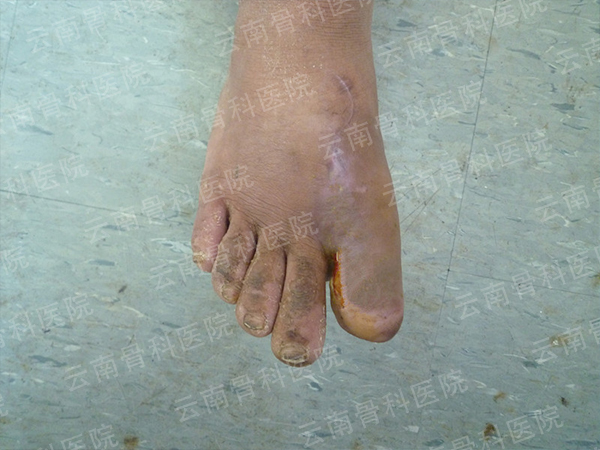

拇指Ⅱ度再造